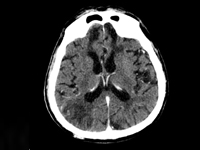

InternaNa świecie, w tym również w Polsce, obserwuje się systematyczny wzrost udziału w populacji ogólnej ludzi w wieku podeszłym. Starzenie się społeczeństwa oraz wiążący się z tym wzrost liczby pacjentów geriatrycznych stanowi obecnie kolejne z wyzwań, któremu sprostać musi medycyna XXI wieku. Pacjent geriatryczny według definicji Światowej Organizacji Zdrowia WHO (World Health Organization), to chory, który osiągnął przynajmniej 60 lat. Badanej osobie towarzyszy zazwyczaj znaczna ilość chorób, co jest typowe dla wieku starczego i współistnieje z ryzykiem nagłego pogorszenia stanu zdrowia lub zgonu [1]. Zgodnie z potrzebą, na całym świecie wdraża się szereg rozwiązań, prowadzących do udoskonalenia gałęzi medycyny jaką jest geriatria. Kompleksowa ocena geriatryczna (Comprehensive geriatrc assessment, CGA) to narzędzie, na które składa się zespół skal i testów, które pozwalają na holistyczną ocenę pacjentów ułatwiając wykrycie przyczyny pogorszenia się stanu zdrowia i wybór optymalnej terapii. Pełna ocena pacjenta w zależności od jego stanu klinicznego trwa od 30 do 60 minut [2]. Choroby współistniejące oraz leki przyjmowane przez pacjentów geriatrycznych niejednokrotnie wymagają znacznej modyfikacji ogólnie przyjętych standardów leczenia. Duża liczba stanów nagłych u pacjentów w wieku podeszłym przebiega z zaburzeniami świadomości. Trudności w prawidłowym postrzeganiu otaczającego świata, które napotykają pacjenci w znacznym stopniu komplikują możliwość dokładnego zebrania wywiadu lekarskiego, jak również przeprowadzenie badania fizykalnego i wdrożenie właściwych działań diagnostyczno-leczniczych.